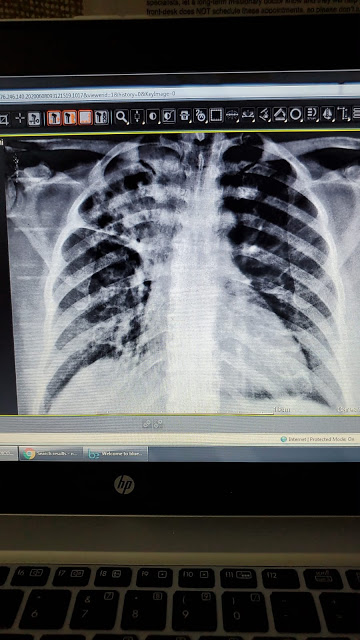

The above x-ray was done on the same 6 year old girl, finding significant constipation. We did the x-ray to see if there was concomitant constipation to see if ‘dysfunctional elimination syndrome’ was the cause of her symptoms or certainly an odd neurological disorder (she did not have any other neuro findings on exam). We are still working on caring for this little girl and appreciate prayers for her. We are thankful that her mother finally is pursuing treatment for her condition which had been going on for at least the past 3 years.

Below is a chest x-ray of a patient that Dr Nathan diagnosed tuberculosis in this past week and a photo I shot with my iPhone down the lens of the microscope looking for the pink staining rods on an AFB stain. (Its a bit difficult to appreciate, being more obvious looking through the microscope.) The third photo is demonstrating free air under the diaphragm. The x ray significance of that finding is that it indicates there is an abdominal perforation somewhere and a life-threatening surgical emergency exists. The patient ended up being HIV positive and had a spontaneous perforation without any history of abdominal surgery. He had not been undergoing any treatment for his HIV. After successful surgery, we referred him on to the HIV treatment center in La Ceiba.